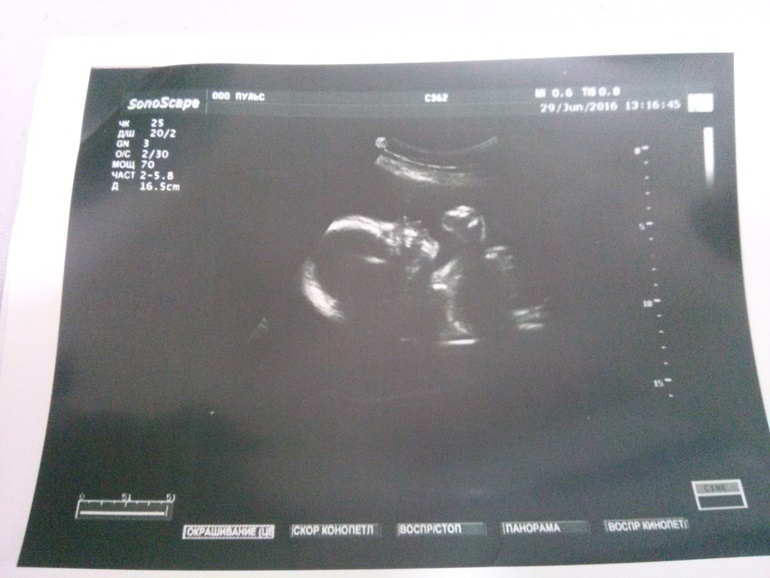

Анна 9 лет Я 25 неделек В животике доченька Виктория!!! Кулачок нам от доченьки)))) Посмотрите еще 20 записей на эту тему Отменить Ответить Надежда( сменила аву Надюха с ручками)) красатулька!!!!!! Растите здоровенькие! 29.06.2016 Ответить Анна Спасибо!!!!!!!!!!!!!!! 29.06.2016 Ответить Низко головка ребенка! А к нам пришла посылочка от ФЕИ!!!!!! Чаты Беременных Выберите чат: Январята-2026 Февралята-2026 Мартята-2026 Апрелята-2026 Майчата-2026 Июнята-2026 Июлята-2026 Августята-2026